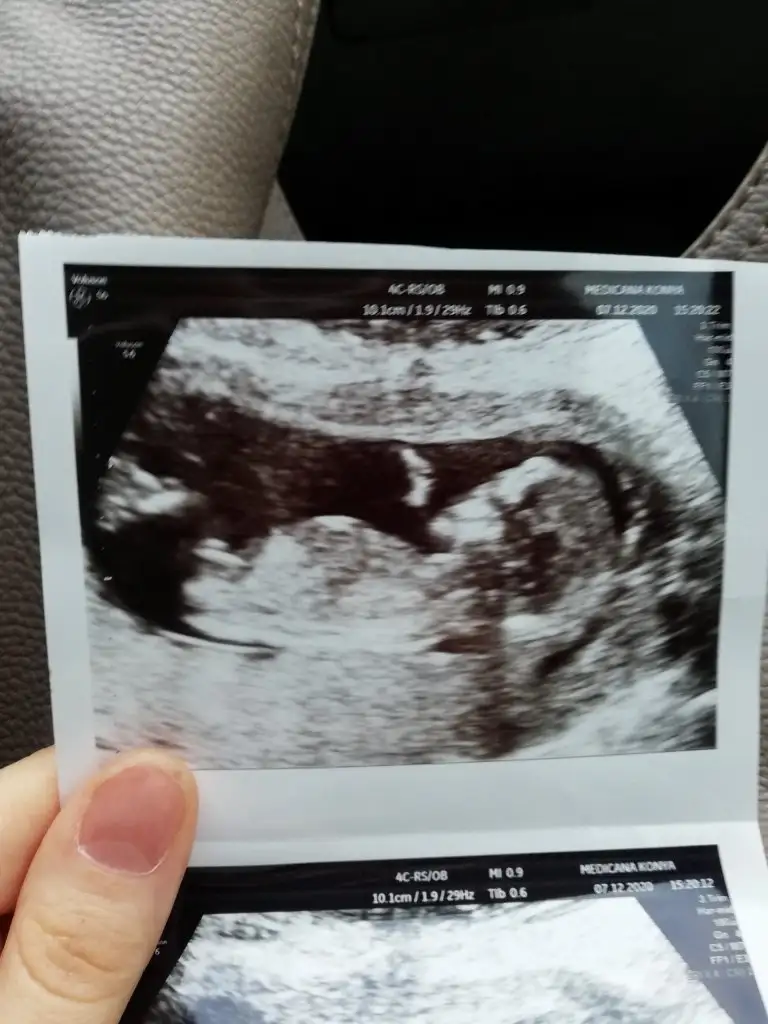

Insallah canim bi kizim varerkek gibi canim çıkıntı olan yer karanlık baya ama erkeğe benziyo

ErkekMerhaba benim bebegim içinde bir bakanilirmisiniz acaba.

erkek gibi geldiMerhaba benim bebegim içinde bir bakanilirmisiniz acaba.

Vallah kizlar Bende erkek hissediyorum yinede sormak istedim tesekkur ederimerkek gibi geldi

Kz gibi geldiKizlar buda baska bir açidan ugs’si

Iste diger resimlerdede erkek gibiKz gibi geldi